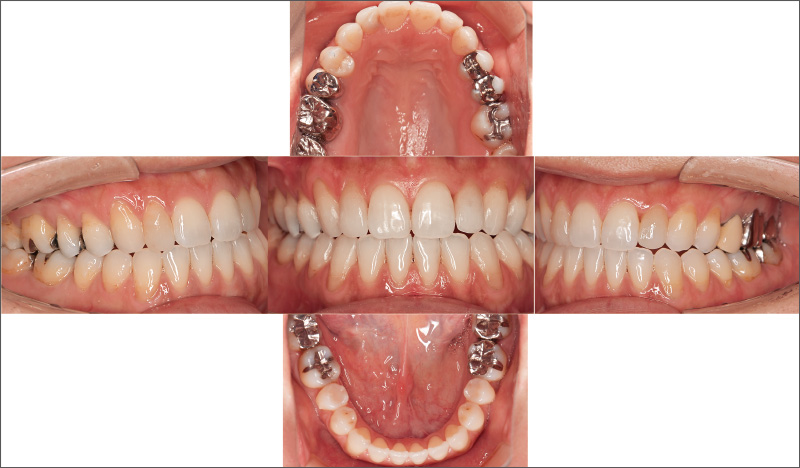

安定した口腔内を保つ30代女性。前歯の叢生と左右非対称であることが気になり、「iGo」での治療を希望。₅ ₅が舌側傾斜する鞍状歯列弓で、₆₅ ₅₆の咬頭嵌合位での咬合が確立されておらず、将来的に咬合が理由で前歯にトラブルが起こる可能性があることから、咬合再構成を提案しました。歯科における一般開業医の役割は、患者さんの口腔内が安定し、10年後、20年後も歯を失わずにいられる方法を考えることです。主訴だけでなく、口腔内の長期安定のため咬合までしっかりと診て適切なコンサルテーションを行い、治療につなげていくことが重要です。

![[写真] 前歯の叢生と左右非対称であることを主訴に来院した30代女性](/academic/dentalmagazine/wp-content/uploads/sites/2/2025/09/194-5_photo11.jpg)

症例3-1 前歯の叢生と左右非対称であることを主訴に来院した30代女性。「iGo」による前歯部矯正治療に加えて、₅ ₅を立ち上げて、咬合再構成を行うことを提案した。 -

![[写真] 叢生の改善に加え、咬合の安定を得ることができた](/academic/dentalmagazine/wp-content/uploads/sites/2/2025/09/194-5_photo12.jpg)

症例3-2 叢生の改善に加え、咬合の安定を得ることができた。表層だけでなく、深層までしっかり診て判断し、対応することが大切である。